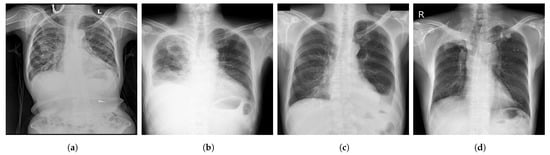

- CheXpert [44] is a large Public dataset of CXR images composed of 224,316 images acquired from 65,240 patients. It contains 14 common chest abnormalities, and it was collected from the Hospital of Stanford between 2002 and 2017. Each image in CheXpert dataset was labeled for the presence of 14 abnormality as negative, positive, or uncertain based on an automated rule-based labeller to extract the observations of experts from the free text radiology reports. Samples of CXR images from CheXpert are shown in Figure 3.

Figure 3.

Samples of CXR images from CheXpert dataset [44] where, (a) Atelectasis; (b) Cardiomegaly; (c) Edema; (d) Pneumonia.